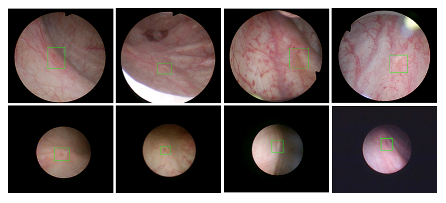

漫画同人 医疗机器人研究院—深睿医疗人工智能医学视频联合实验室成立于2018年7月。PI包括来自于交大生医工学院和电院的三位教授,平台建设目标是将人工智能实时地用到临床医学中去,研究方向包括:1. 建立内窥镜人工智能辅助诊断系统,通过对病灶和解剖结构的实时识别来辅助医生更好地进行微创诊断和治疗;2. 以个性化、定量化的精准诊疗技术为研发目标,重点开展医学影像智能诊断、医学可视化及计算机辅助手术规划、AI及大数据分析在临床诊疗流程中的集成应用等方向的研发。试图利用AI技术、大数据分析技术、3D打印技术、虚拟现实及增强现实技术促进临床的影像诊断、治疗方案设计、预后预测分析等诊疗环节的智能化提升与技术变革;3. 面向运动医学康复、神经退行性疾病量化诊断,以及其他与人体运动相关的疾病诊疗、康复应用,开展视觉三维人体运动的测量、分析与识别研究,通过基于深度学习的视觉检测识别以及相关大数据分析,为相关疾病的诊疗和康复提供AI辅助。具体临床应用包括:关节镜手术术后康复指导和评估、帕金森病的量化诊断、精神疾病的量化诊断与评估、儿童异常行为分析等。

近年来,联合实验室发展了泌尿镜手术实时识别技术,人体姿态精确识别技术,另外围绕小儿先心病手术、肝癌消融手术、数字口腔诊疗的智能化提升等内容进行应用研发。